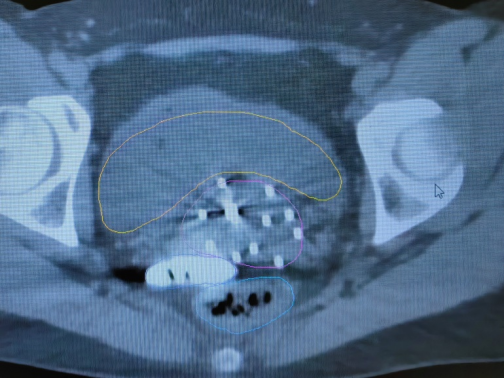

2. 無(wú)痛近距離插植治療:近距離插植治療是將宮腔管和插植針等施源器的置入宮頸及宮旁病灶組織的一種放療方式,由于老年患者陰道狹窄、對(duì)疼痛耐受性差,很多難以配合治療,甚至拒絕治療,導(dǎo)致腫瘤無(wú)法得到根治。我院婦科放化療采取靜脈麻醉下給予患者無(wú)痛插植治療,能夠最大程度上減少治療過(guò)程中患者的疼痛感和恐懼感,使得治療得以順利進(jìn)行,避免因中斷治療帶來(lái)的劑量缺陷,提高患者腫瘤的局部控制率,極大提高患者治療舒適度及依從性。

*無(wú)痛插值靶區(qū)

正是這種環(huán)環(huán)相扣、科學(xué)完善的 “精準(zhǔn)打擊 + 全程護(hù)航” 規(guī)范診療模式,讓馬阿姨這樣的腫瘤晚期患者也能獲得根治性治療機(jī)會(huì)。